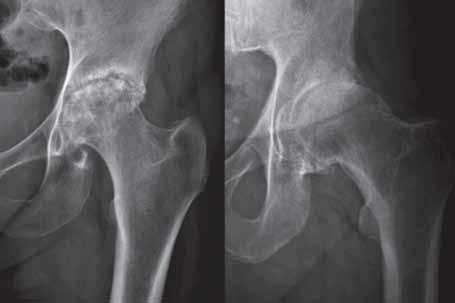

Rycina 2.9.

Zwężenie szpary stawu biodrowego u dwóch różnych osób. Po stronie lewej koncentryczne, z obecnością geod i nadżerek powierzchni stawowych – obraz wskazuje na chorobę zapalną (możliwość współistnienia jałowej martwicy aseptycznej głowy kości udowej).

Po stronie prawej zwężenie w części górnej, z obecnością osteofitozy wieńcowej i przebudowy sklerotycznej wewnętrznej części szyjki kości udowej, przy braku obecności nadżerek powierzchni stawowych – obraz wskazuje na chorobę zwyrodnieniową.